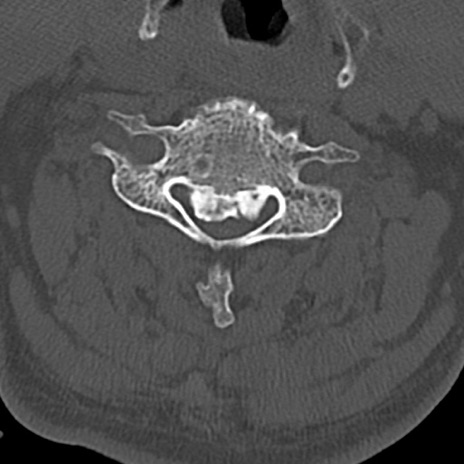

頚椎CT

横断像